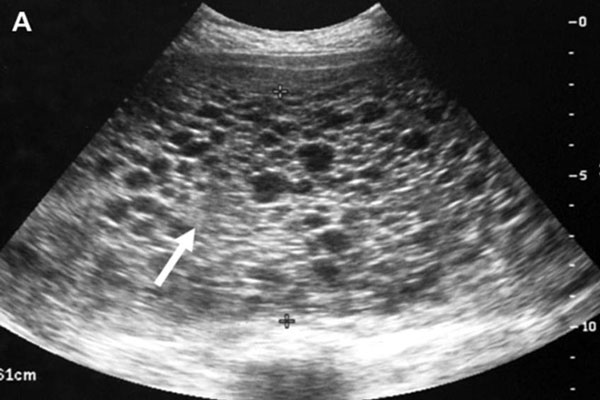

Có thai ngoài tử cung cũng là nguyên nhân siêu âm không thấy thai

Thông thường, trứng sẽ về tử cung của mẹ làm tổ sau khi thụ tinh. Nhưng đôi khi ở những tình huống bất thường, trứng sẽ làm tổ ở một vị trí khác ngoài tử cung. Đây chính là lý do vì sao thử que thấy 2 vạch nhưng siêu âm thì không nhìn thấy thai.

Bác sĩ sẽ tiến hành làm thêm một số xét nghiệm khác để có kết quả chính xác nếu đã có nghi ngờ mang thai ngoài dạ con. Khi đã được chẩn đoán có thai ngoài tử cung, mẹ nên đình chỉ vì có thể dẫn đến nhiều biến chứng rất nguy hiểm cho mẹ như vỡ buồng trứng.

Mang thai trứng có thể là nguyên nhân siêu âm không thấy thai

Đây là một trong những nguyên nhân mà chị em có thể gặp. Đây có thể gọi là một căn bệnh khá nguy hiểm. Nó xảy ra khi trứng đã được thụ tinh nhưng lại gặp một vài rối loạn khác dẫn đến tăng sinh những tế bào gai nhau làm những mao mạch, những mô liên kết với mẹ phát triển không kịp, gây phù nề, thoái hóa. Lúc này, thay vì phát triển thành thai nhi, trứng sẽ tăng sinh và trở thành những bọc nhầy như trứng ếch.

Có hai loại mang thai trứng: toàn phần và bán phần. Khi tinh trùng bình thường kết hợp với trứng bất thường thì gọi là thai trứng toàn phần. Ngược lại, khi trứng bình thường kết hợp với 2 tinh trùng bình thường nhưng quá trình thụ tinh bất thường thì gọi là thai trứng bán phần. Dù ở trường hợp nào thì mẹ cũng nên loại bỏ để không để lại nguy hiểm.